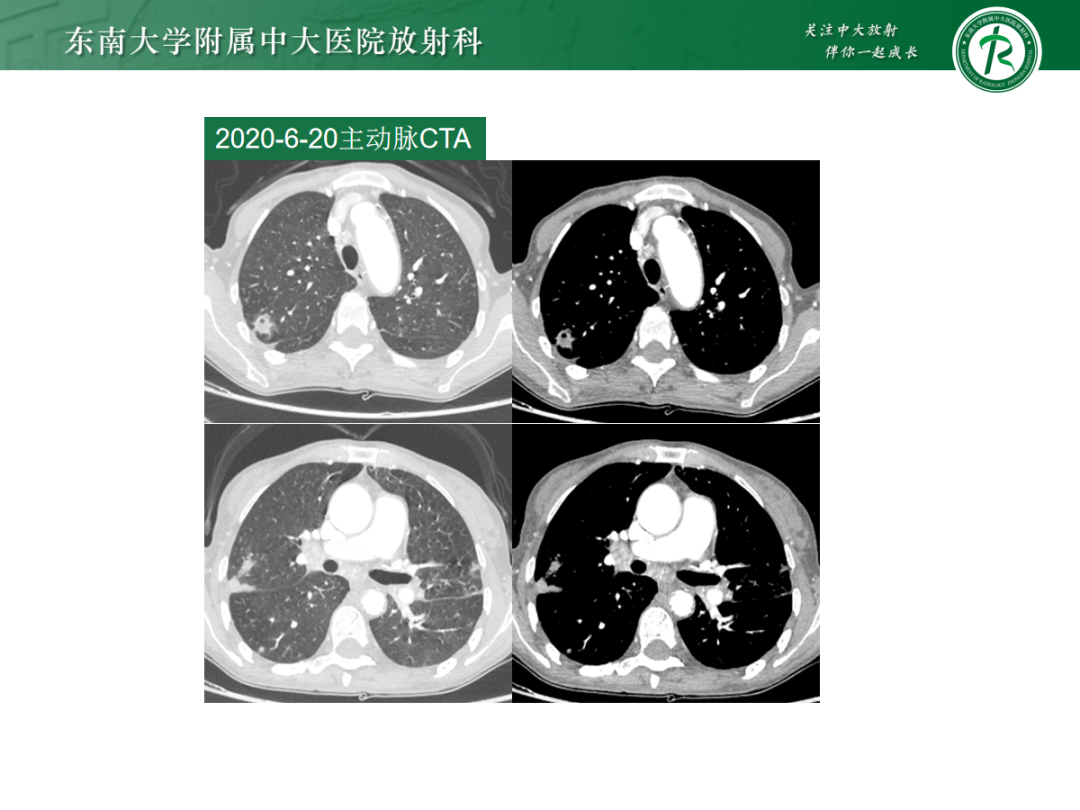

肺内多发空洞及“树芽征”疾病的影像诊断及鉴别

来源:东南大学附属中大医院放射科